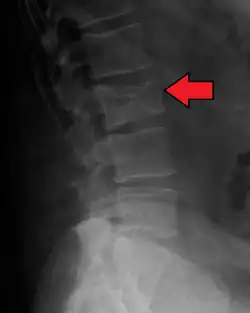

Bone pain

Bone pain affects almost 70% of people with multiple myeloma and is one of the most common symptoms.[2]: 653 [23] Myeloma bone pain usually involves the spine and ribs and worsens with activity. Persistent, localized pain may indicate a pathological bone fracture. Involvement of the vertebrae may lead to spinal cord compression or kyphosis. Myeloma bone disease is due to the overexpression of receptor activator for nuclear factor κ B ligand (RANKL) by bone marrow stroma. RANKL activates osteoclasts, which resorb bone. The resultant bone lesions are lytic (cause breakdown) in nature. They are best seen in plain radiographs, which may show "punched-out" resorptive lesions (including the "raindrop" appearance of the skull on radiography). The breakdown of bone also leads to the release of calcium ions into the blood, leading to hypercalcemia and its associated symptoms.[24]

The diagnostic examination of a person with suspected multiple myeloma typically includes a skeletal survey. This is a series of X-rays of the skull, axial skeleton, and proximal long bones. Myeloma activity sometimes appears as "lytic lesions" (with local disappearance of normal bone due to resorption) or as "punched-out lesions" on the skull X-ray ("raindrop skull"). Lesions may also be sclerotic, which is seen as radiodense.[76] Overall, the radiodensity of myeloma is between −30 and 120 Hounsfield units (HU).[77] Magnetic resonance imaging is more sensitive than simple X-rays in the detection of lytic lesions. An MRI may supersede a skeletal survey, especially when vertebral disease is suspected. Occasionally, a CT scan is performed to measure the size of soft-tissue plasmacytomas. Nuclear Medicine Bone scans are typically not of any additional value in the workup of people with myeloma (no new bone formation; lytic lesions not well visualized on nuclear bone scan).

Pathological fracture of the lumbar spine due to multiple myeloma -